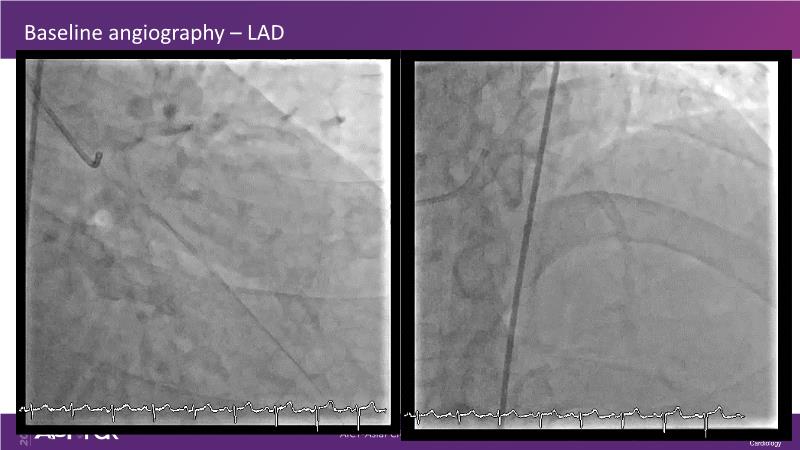

Beginning with the end in mind - FFR vs. IVUS imaging

Consult this session if you want to explore different plaque modification techniques and technology and see how to maximise PCI outcome with IVUS imaging. Also assess when to select FFR to determine when to treat vs. IVUS to determine where and how to treat.